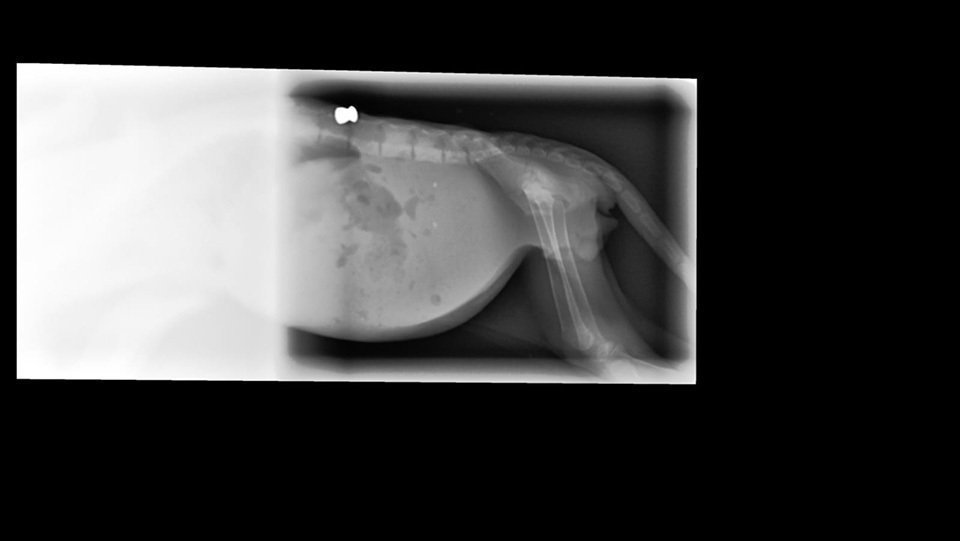

Ens van portar un gat al Centre Veterinari d'Almacelles i vam comprovar que estava desnodrit (pesava 340 grams) i que no tenia mobilitat al terç posterior, afectant les extremitats posteriors i cua. En fer unes radiografies vam comprovar que li havien disparat amb una escopeta de balins i que un balí de copa li havia provocat una lesió a la columna vertebral.

El balí el vam treure aquesta setmana, ja que, a causa de una úlcera que s'ha fet en un ull, hem hagut d'operar-lo per intentar salvar-li l'ull, i hem aprofitat per treure el balí que es palpava perfectament a l'abdomen, darrere de l'última costella, a prop de la columna.